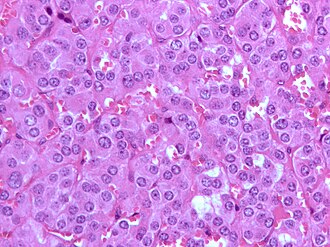

Pheochromocytoma. H&E stain. | |

| LM | Zellballen (nests of cells), fibrovascular septae, salt-and-pepper nuclei, +/-hemorrhage (very common) |

- Chief cells:

- Usu. polygonal cells, may be spindled.

- Arranged in cell nests - "Zellballen" (literally cell balls) - key feature.

- Stippled chromatin (AKA salt and pepper chromatin) - coarsely granular chromatin.

- Granular cytoplasm, often basophilic - important.

- Sustentacular cells (structural support cell).

- Often haemorrhagic - highly vascular.

- +/-Nuclear pleomorphism.

The sections shows a partially hemorrhagic lesion in the medulla of the adrenal gland that is arranged in nests (Zellballen). The tumour cells have abundant grey/blue granular cytoplasm, and nuclei with granular chromatin (salt and pepper chromatin). The lesion is surrounded by a compressed rim of adrenal cortex and fibrosis tissue. The core of the lesion is fibrotic and has clusters of hemosiderin-laden macrophages.